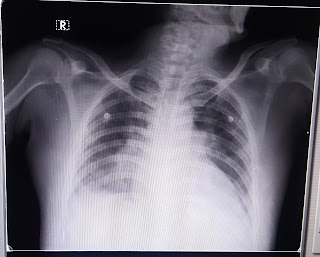

RS - BAE +, NVBS heard